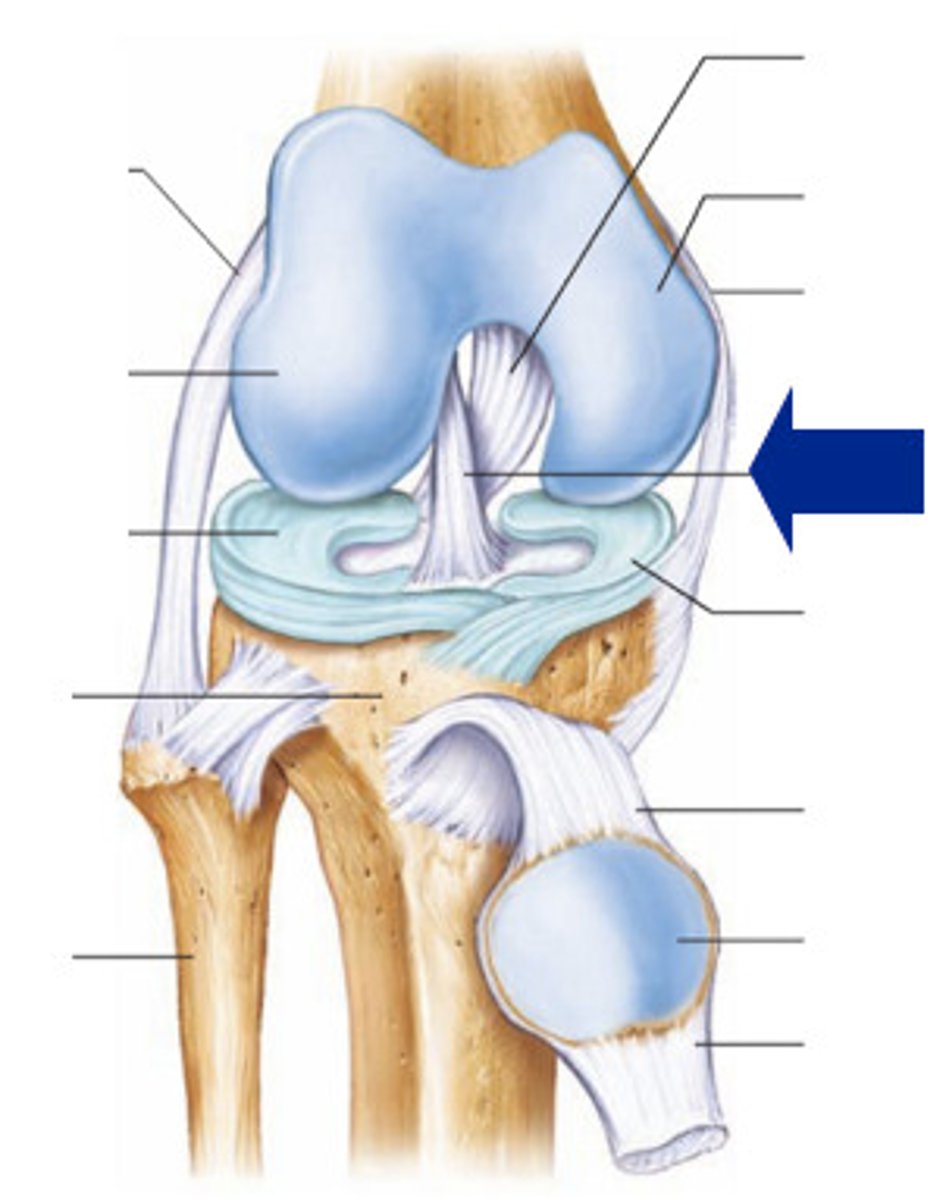

Medial meniscus

Lateral meniscus

Anterior cruciate ligament

Posterior cruciate ligament

Medial (tibial) collateral ligament

Lateral (fibular) collateral ligament